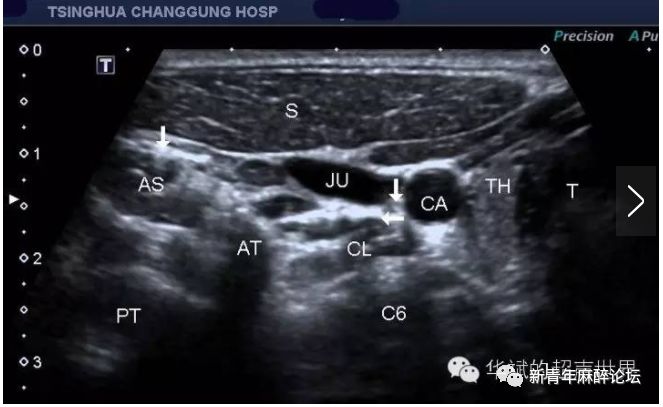

图1 超声引导第六颈椎平面超声图像(引自:张华斌 华斌的超声世界)

(图1 第六颈椎横突水平横断。T:气管,TH:甲状腺,CL:颈长肌,C6:第六颈椎,CA:颈总动脉,JU:颈内动脉,AT:第6颈椎横突前结节,PT:第6颈椎横突后结节,AS:前斜角肌,S:胸锁乳突肌。左边箭头:膈神经,右边箭头:迷走神经。水平箭头:颈长肌前筋膜。)

由上图可以看到,在第6颈椎横突前结节周围有很多重要的血管神经结构,水平箭头所示的位置为颈长肌的前筋膜,其内并没有显示显著的星状神经节结构,因此,针对此处的阻滞需要较大的药量才能浸润到实际位置靠下的星状神经节。所以临床实际操作过程中我们一般选择C6- C7横突间行星状神经节阻滞或直接选择C7横突水平行星状神经节阻滞。